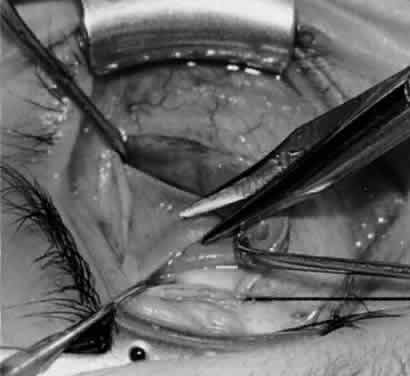

Fig. 33. A 6-0 Vicryl suture is placed in the inferior oblique muscle in preparation for anterior transposition. A Green muscle hook is placed beneath the inferior rectus muscle.

Fig. 34. The eye is retracted nasally with a Green muscle hook. The anterior suture is placed just anterior and temporal to the insertion of the inferior rectus muscle. The posterior suture is applied about 10 mm temporal to the inferior rectus muscle on a line that would be continuous with the inferior rectus insertion if it were extended temporally.

Fig. 35. The suture is tied, and the inferior oblique muscle is in the position for anterior transposition. The inferior rectus muscle is retracted nasally on the Green muscle hook, and the Desmarres lid retractor is placed inferior temporally.